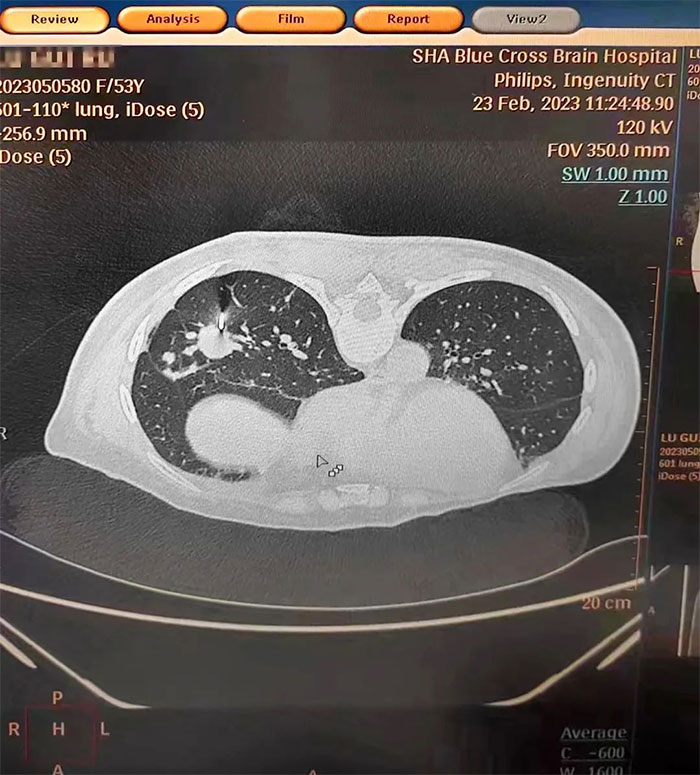

▲ 肺CT显示,穿刺针穿刺到位

在明确告知风险并经家属同意后,张泽明主任在CT引导下精准定位,选择合适的进针位置,一次穿刺成功,顺利取得组织样本。手术过程顺利,未出现明显并发症。经送检,术后病理诊断为腺癌,结合临床病史符合乳腺癌转移,为制定下一步个体化综合治疗方案提供了重要依据。